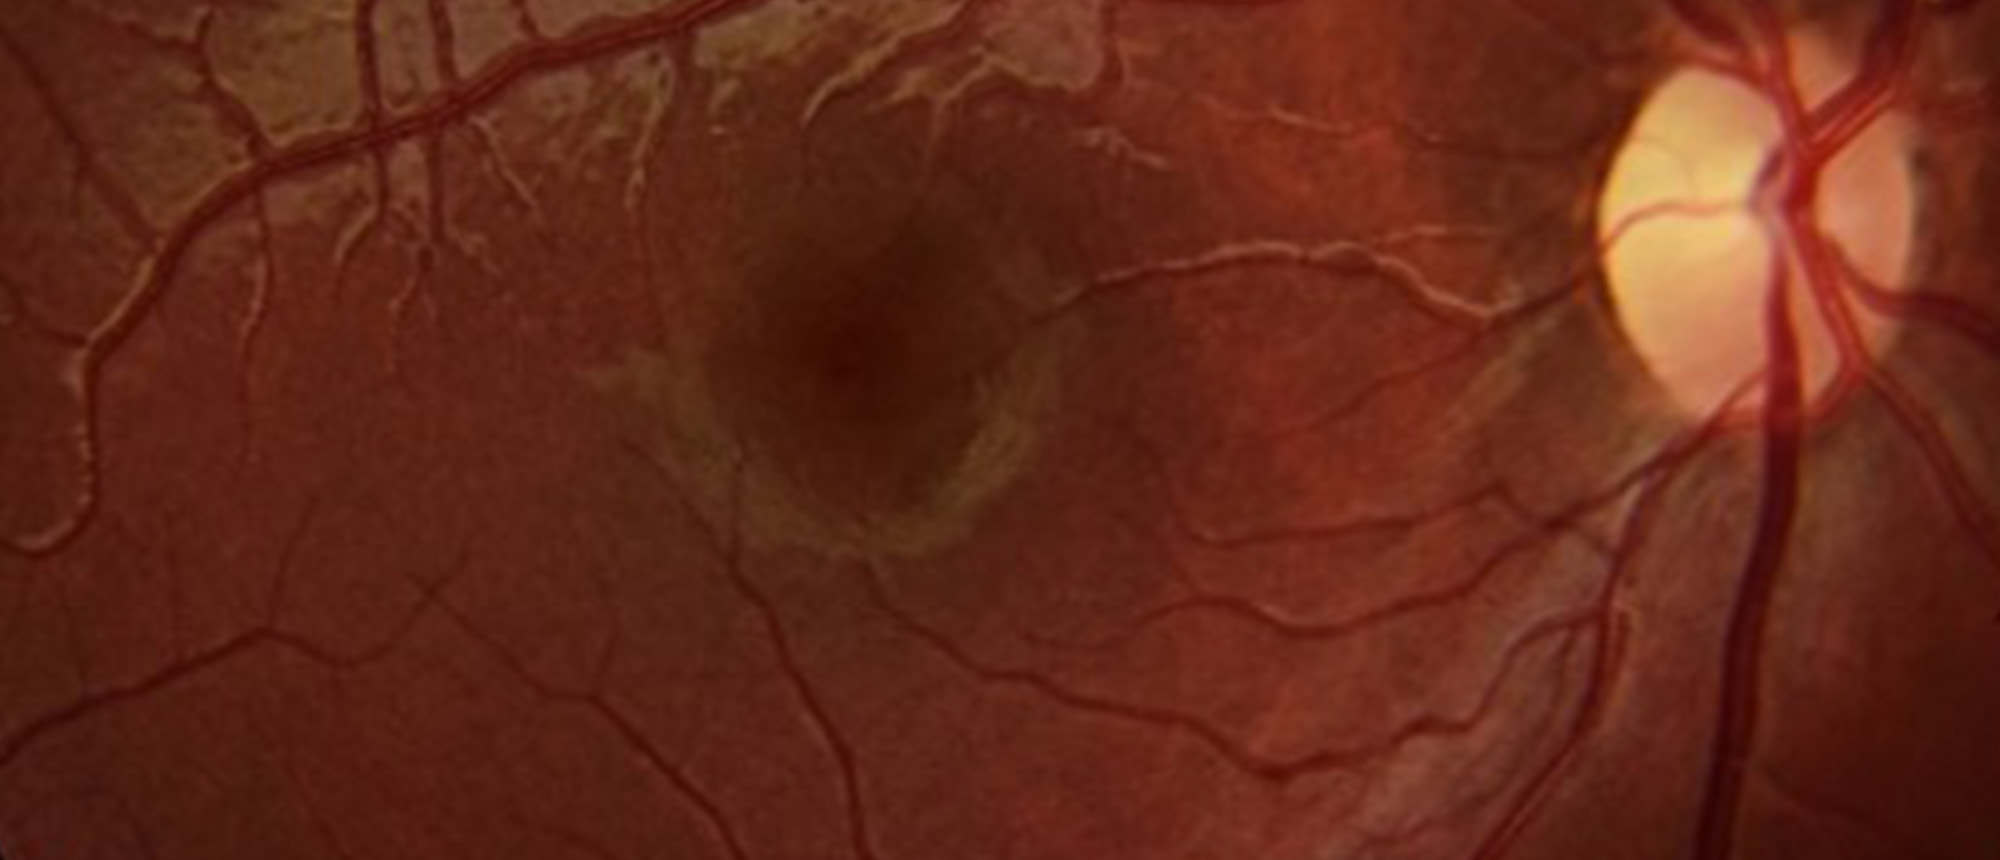

Morning Glory Disc Anomaly A child presented for evaluation of chronic poor vision of her right eye. Fundus exam showed an excavated nerve with peripapillary chorioretinal pigmentation, overlying central glial tuft, radial vessels, and inferior serous retinal detachment. Findings were consistent wi…